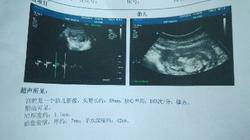

我末次月经是3月22号 一般月经推迟一个星期那么我的宝宝应该是多少周?b c显示才十二周 是我宝 我末次月经是3月22号。一般月经推迟一个星期。那么我的宝宝应该是多少周?b c显示才十二周。是我宝宝偏小吗? 点击展开 一个比奥利奥还傲的女人╰ 2014-07-10 02:42 为您推荐: 其他回答 医院发的小册子上有标注。 asdavx456s 2014-09-01 23:38 您好,只要宝妈妈多注意点自己的饮食营养,多休息,定期的去检查胎儿发育好就行,祝孕妈妈健康快乐 asdavx456s 2014-07-11 11:11 相关问题 5月9号来月经现在没来 宝宝几周了 生完宝宝后三个月一直有恶露,从第四个月开始就半个月来一次月经,我感觉不正常,身边的宝妈都没有,我是 2012年11月22生的宝宝,去年又引产,之后就上环的,最近两个月宝宝就是自己带的,上个月月经来了